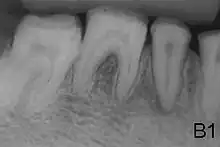

- Enamel of abnormal thickness due to malfunction in enamel matrix formation. Enamel is very thin but hard & translucent, and may have random pits & grooves. Condition is of autosomal dominant, autosomal recessive, or x-linked pattern. Enamel differs in appearance from dentine radiographically as normal functional enamel.[20]

- Type 2 - Hypomaturation

- Enamel has sound thickness, with a pitted appearance. It is less hard compared to normal enamel, and are prone to rapid wear, although not as intense as Type 3 AI. Condition is of autosomal dominant, autosomal recessive, or x-linked pattern. Enamel appears to be comparable to dentine in its radiodensity on radiographs.